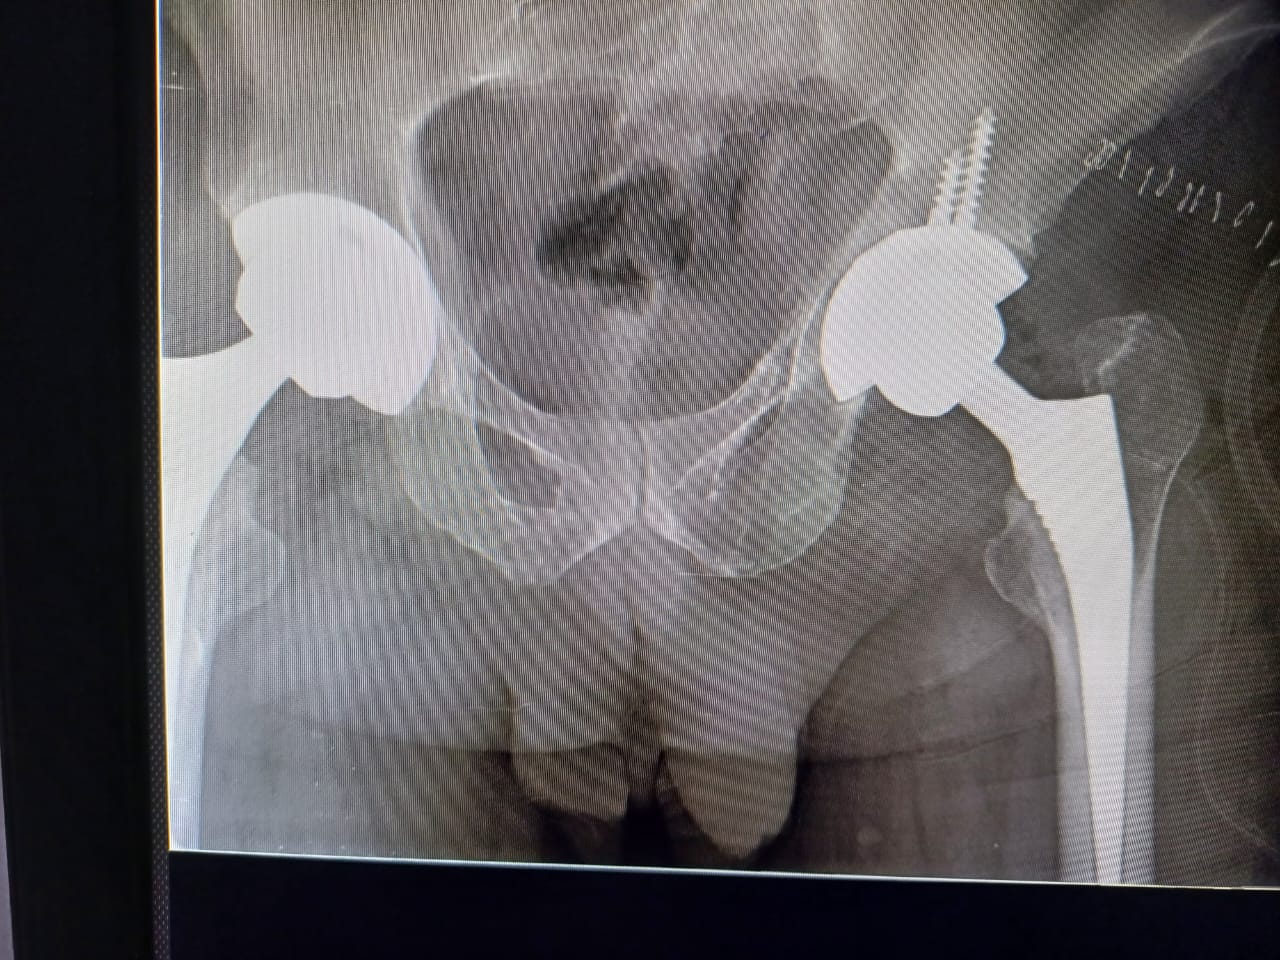

There are two primary types of hip replacement surgeries: total hip replacement (THR) and partial hip replacement (PHR). In THR, both the ball (femoral head) and socket (acetabulum) of the hip joint are replaced with artificial components. PHR, on the other hand, involves replacing only the damaged femoral head, preserving the natural socket. The choice between the two depends on the patient’s condition, age, and activity level.

Modern hip replacement techniques often involve minimally invasive procedures that reduce tissue damage and speed up recovery. Advanced implants made of durable materials like metal alloys, ceramics, and high-grade plastics are designed to closely mimic the natural movement of the hip joint. Surgeons may also use robotic-assisted systems to ensure precise alignment, enhancing the longevity and functionality of the implant.